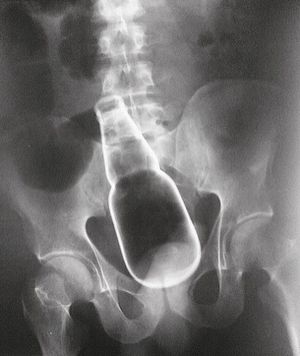

This X-ray belongs to a 35-year-old man who presented to the emergency department with profuse rectal bleeding, abdominal pain, and an altered mental status. He was found intoxicated with a low blood pressure of 70/40 mm Hg and a foreign body was found on rectal examination but was not visible and no evidence of trauma was detected. Once the patient was hemodynamically stable, he was sent to be X-rayed and what was found was shocking as far as it can get to. An intact bottle was seen in the rectosigmoid colon. Laparotomy revealed a glass bottle of beer lodged in the sigmoid colon, with multiple associated lacerations in the rectosigmoid colon. The bottle was removed in surgery, and the man was treated with antibiotics and pain relievers after which he recovered uneventfully.